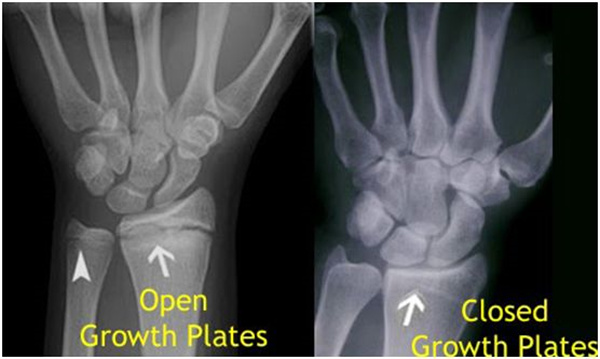

其實想要了解孩子的生長發(fā)育情況或者說孩子未來身高的趨勢,測骨齡是個好辦法。臨床上通常拍攝兒童的左手正位X光片 , 采用《中華-05》骨齡標(biāo)準(zhǔn)對手腕骨發(fā)育程度進行骨齡評價。

我們都知道,人體的高矮是由骨骼的生長發(fā)育決定的,特別是下肢長骨。長骨呈長管狀,在長骨的兩端有一種專管骨骼生長的骺軟骨,它與干骺端之間有一盤狀軟骨結(jié)構(gòu)稱為骺板(線),在幼兒的X光片上表現(xiàn)為一條較寬的透光帶。(見下圖)

未成年時隨著年齡的增加骺軟骨端不斷骨化,骨骼就不斷增長。當(dāng)骨骺線完全閉合時骨骼就停止生長,個子也就不再增長了。一般骨骺端完全閉合的年齡是18~20歲左右。